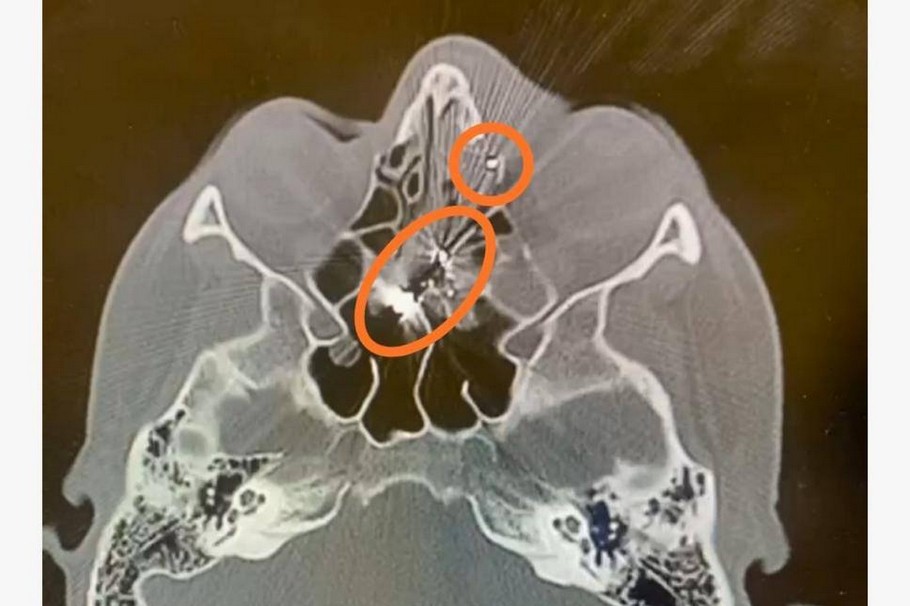

Далі – транспортування до Кам’янської лікарні швидкої медичної допомоги, де під час комп’ютерного обстеження було виявлено проникаюче кульове пневматичне поранення лівої очниці.